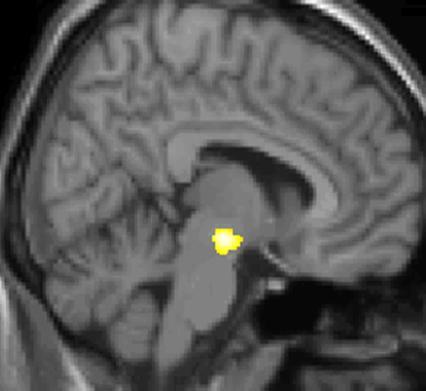

В этом исследовании ещё одна деталь добавляет объёма: у людей измерили базовую доступность A1-рецепторов и посмотрели, связано ли это с величиной изменений серого вещества. Оказалось, что более низкая исходная доступность субкортикальных A1-рецепторов предсказывала более выраженное снижение сигнала серого вещества в кофеиновой группе (почти во всех областях, кроме таламуса).

То есть «реакция на кофеин» тут не только вопрос привычки. Это ещё и вопрос того, какая у тебя базовая нейрохимическая конфигурация.

Таламус ведёт себя как отдельная планета

Таламус в их выводах выглядит почти упрямым. Он и реагирует заметно, и восстанавливается не так быстро, и связь с A1-рецепторами у него не такая прямолинейная, как у других кластеров. Авторы прямо обсуждают, что таламическая пластичность может идти через иные механизмы и что будущие работы должны внимательнее посмотреть на A2A-рецепторы.